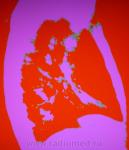

Возможности "цветовой" обработки цифрового изображения молочной железы.

Вот Евгений Иванович, мы пробовали в своё время.

И ещё.